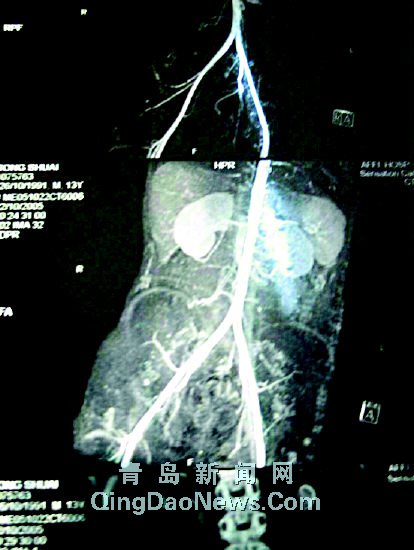

| 从小可的CT片可以明显看出长了4个肾。格宁为鹏摄 |

CT片显示4个肾

在青医附院小儿外科,记者见到了小可的一张CT片。在杨主任的介绍下,记者在上面清楚地看出小可的肾脏情况,一边明显有两个肾脏,一边不明显,但也是由两个肾重叠而成。杨主任认为,虽说这也是一种畸形现象,好在它们的基本功能比较正常。除此之外,小可的病情与最初通过外观诊断的相差无几,主要是膀胱外翻、尿道闭锁和膀胱直肠漏。